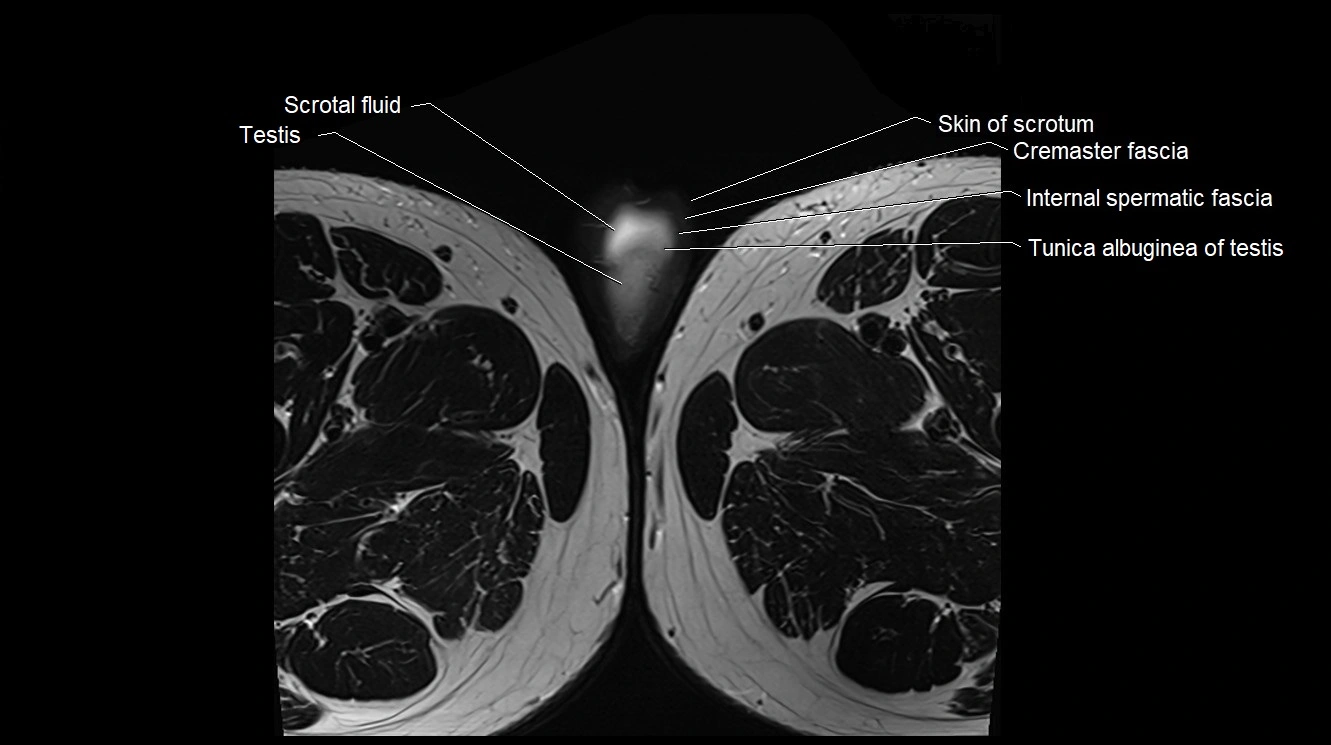

- Cremaster fascia

- Cremaster muscle

- Internal spermatic fascia

- Scrotal fluid

- Skin of scrotum

- Testis

- Tunica albuginea of testis